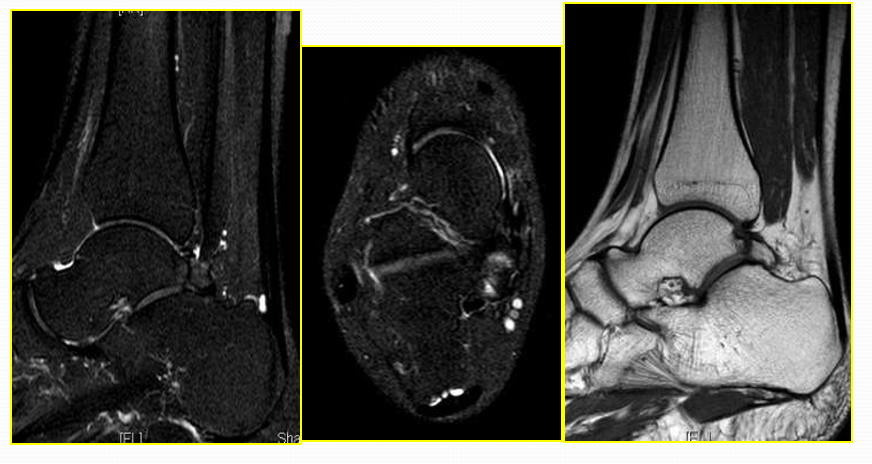

跟腱滑囊炎

足在中立位且轻度跖屈时的矢状面和横断面T2WI是显示滑囊炎和跟腱病变的理想检查方位。当有跟腱前滑囊炎存在时,T2WI上正常跟腱前脂肪消失。合并骨质侵蚀和跟骨后上方骨刺

三角籽骨综合征

病因病理机制:

• 多见于经常跖屈的患者,如芭蕾舞演员、登山运动员、足球运动员

• 三角籽骨位于距骨后缘

• 足强制性跖屈导致胫骨后下缘或跟骨上缘撞击

• 三角籽骨、距骨后三角、周围软组织、肌腱损伤(后踝撞击综合征)

• 临床表现为后踝疼痛,活动受限

MR表现:

• 三角籽骨或距骨后三角结构模糊和变形,T1WI信号降低, T2WI信号升高

• 周围脂肪水肿

• 屈踇趾长肌腱信号升高,见鞘膜积液

• 胫骨后下跟骨上缘骨结构形态变化和信号异常。

• 三角籽骨和距骨退行性囊变